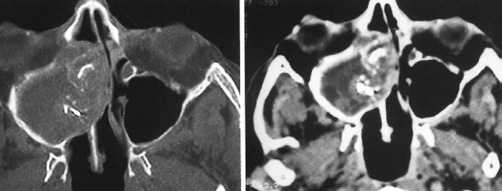

Eine kugelige homogene Verschattung in der Höhle wird im Rahmen der zahnmedizinischen und HNO-Behandlung häufig beobachtet (Abb. 5). Schmerz oder Druckgefühl werden in der Regel nicht angegeben. Bei diesen Retentionszysten handelt es sich oft um Zufallsbefunde, die bei bis zu 14% der Bevölkerung industrialisierter Länder gesehen wurden. Sie sind die Folge umschriebener intraepithelialer Sekretstörungen der Sinusschleimhaut und bedürfen im Falle klinischer Beschwerdefreiheit keiner Behandlung. Nur sehr große Zysten oder homogene Totalverschattungen sollten therapiert werden (Abb. 6). Häufig beklagen die Betroffenen ablaufende Nasensekrete mit unangenehmem Geruch und Geschmack. Im mittleren Nasengang sind endoskopisch eingedickte Sekretbefunde sichtbar (Abb. 7). Besondere Beachtung benötigen inhomogene Verschattungen mit gegebenenfalls sehr dichten Einschlüssen. Hier sind spezifische Infektionen (Pilzball), Tumoren oder Fremdkörper suspekt. Auch im Falle einer deutlichen Restbelüftung muss die Kieferhöhle exploriert und der Befund histologisch geklärt werden (Abb. 8a bis d).

Bei anhaltender klinischer Symptomatik nach erfolgter Zahnbehandlung sollten gegebenenfalls eine rhinochirurgische Behandlung zur Verbesserung der maxillären Clearance und Entfernung des entzündlichen Débris aus der Höhle über einen erweiterten supraturbinalen Zugang eingeleitet werden. Kritisch sind überstopfte Füllmaterialien, da diese gehäuft zur Ausbildung von Pilzkugeln in der KH führen. Histologisch werden dabei überwiegend Pilzhyphen und typische Fruchtköpfe gefunden. Mikrobiologisch lassen sich meist Aspergillus-Stämme nachweisen. Charakteristisch ist die Kalzifizierung der Pilzhyphen, die bei einer Verdichtung kalkdichte Konkremente bilden und als Rhinolithen im CT oder DVT erkennbar werden (Abb. 10) [14]. Einer chirurgischen Sanierung durch vollständige Entfernung des Pilzmaterials über einen erweiterten endonasalen Zugangsweg ist hier der Vorrang einzuräumen [15]. Die Erfolgsrate nach diesen Behandlungen kann als sehr hoch eingeschätzt werden (Abb. 11a und b).